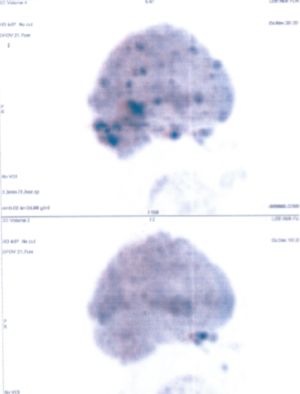

Below are some of the cases, from more than 80 cases we have treated so far with good results. When reading the PET/CT scans, the picture on the left is before treatment, and the picture on the right is after treatment. The intensity of black represents the activity of the cancer, but some black areas are not cancer: brain, heart, radioactive urine in bladder. For the heart, the intensity of black depends on the number of hours of fasting: if more than 10 hours, the heart is not even black, but if fasting is less than 6 hours, it is very black. The intensity of black in the brain can be variable in different scans depending on the brain activity at the time of the scan. The intensity of black in the radioactive urine can also be variable due to the hydration of patients and the time of injection of diuretic.

CASE NO: 31 (LUNG CANCER WITH BRAIN METASTASES)

A 40+ woman with lung cancer and brain metastases failed all treatment including radiotherapy and chemotherapy. She cannot walk. After a few treatment, the left lung cancer is gone, and all the brain metastases are gone. She is starting to walk again. One set of pictures shows the left lung cancer, and the other set of pictures show the brain: on top is BEFORE TREATMENT, bottom is AFTER TREATMENT.

CASE NO: 31 AFTER TREATMENT